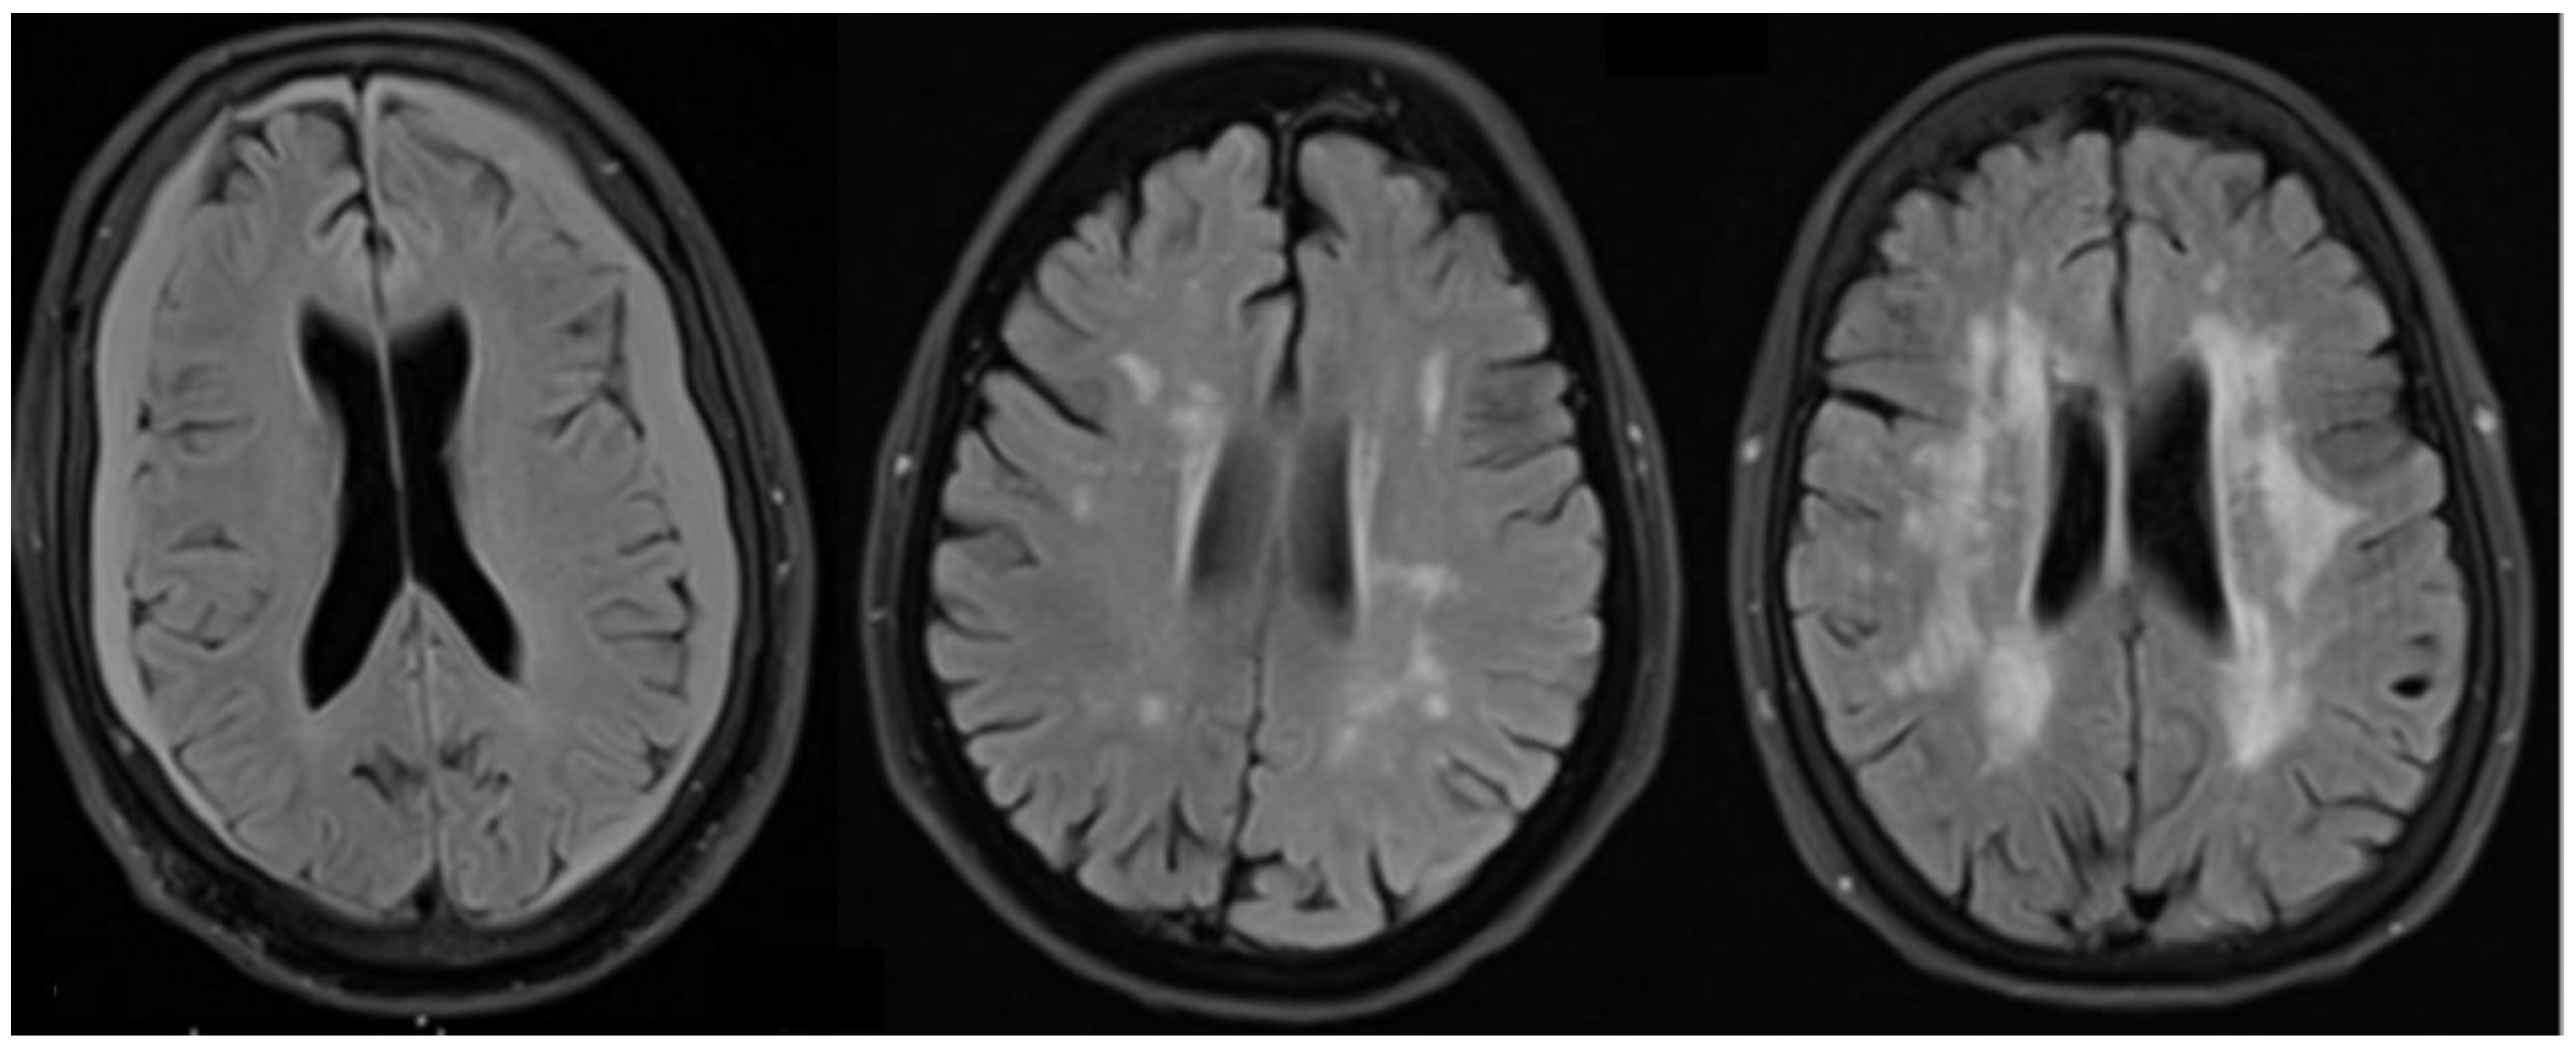

2.8. White Matter Changes in AD

- Nasrabady, S.E.; Rizvi, B.; Goldman, J.E.; Brickman, A.M. White matter changes in Alzheimer’s disease: A focus on myelin and oligodendrocytes. Acta Neuropathol. Commun. 2018, 6, 22. [Google Scholar] [CrossRef] [PubMed]

- Brun, A.; Englund, E. A white matter disorder in dementia of the Alzheimer type: A pathoanatomical study. Alzheimer Dis. Assoc. Disord. 1987, 1, 51. [Google Scholar] [CrossRef]

- Scott, J.A.; Braskie, M.N.; Tosun, D.; Thompson, P.M.; Weiner, M.; DeCarli, C.; Carmichael, O.T.; Alzheimer’s Disease Neuroimaging Initiative. Cerebral amyloid and hypertension are independently associated with white matter lesions in elderly. Front. Aging Neurosci. 2015, 7, 221. [Google Scholar] [CrossRef] [PubMed]

- O’Brien, J.T.; Ames, D.; Schwietzer, I. White matter changes in depression and Alzheimer’s disease: A review of magnetic resonance imaging studies. Int. J. Geriatr. Psychiatry 1996, 11, 681–694. [Google Scholar] [CrossRef]

- Lee, S.; Viqar, F.; Zimmerman, M.E.; Narkhede, A.; Tosto, G.; Benzinger, T.L.S.; Marcus, D.S.; Fagan, A.M.; Goate, A.; Fox, N.C.; et al. White matter hyperintensities are a core feature of Alzheimer’s disease: Evidence from the dominantly inherited Alzheimer network. Ann. Neurol. 2016, 79, 929–939. [Google Scholar] [CrossRef] [PubMed]

- Eloyan, A.; Thangarajah, M.; An, N.; Borowski, B.J.; Reddy, A.L.; Aisen, P.; Dage, J.L.; Foroud, T.; Ghetti, B.; Griffin, P.; et al. White matter hyperintensities are higher among early-onset Alzheimer’s disease participants than their cognitively normal and early-onset nonAD peers: Longitudinal Early-onset Alzheimer’s Disease Study (LEADS). Alzheimer’s Dement. 2023, 19, S89–S97. [Google Scholar] [CrossRef]